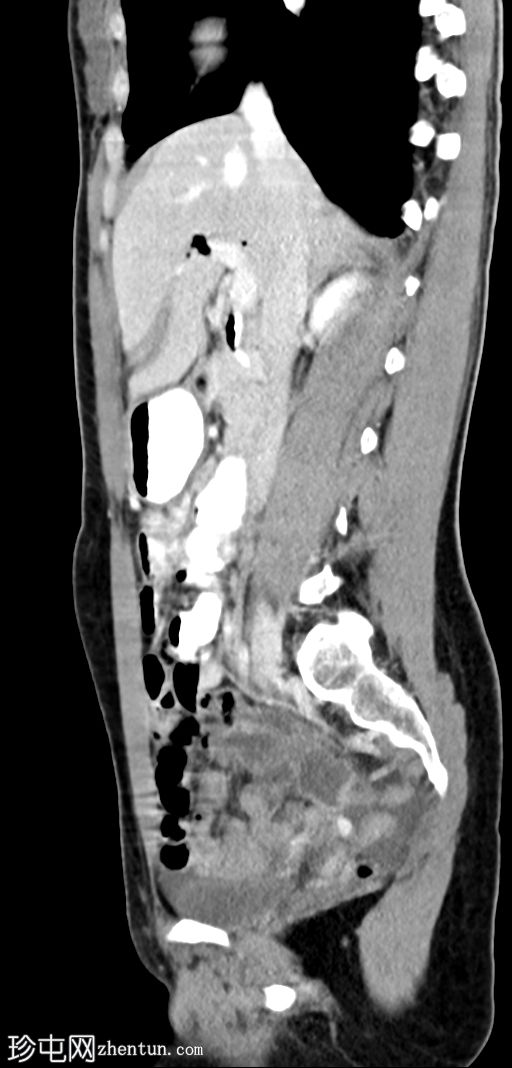

矢状位增强扫描(门静脉期)

肝外胆管、肝内胆管及胆囊内可见气体。后续增强(静脉)检查中加用口服造影剂,结果显示造影剂从十二指肠反流至胆总管,最终进入胆囊。

幽门成形术和迷走神经切断术史可能解释奥迪氏括约肌功能障碍,导致气体和口服造影剂反流至胆道系统。目前有几种关于迷走神经干切断术后奥迪氏括约肌功能障碍的可能机制;该手术会改变括约肌的压力和运动能力。